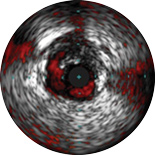

ChromaFlo provides easy assessment of stent apposition, lumen size and more by highlighting blood flow red at the touch of a button. ChromaFlo is available on Philips imaging systems.

Designed to make lumen size and stent apposition instantly recognizable and help identify branches, dissections, thrombus, and plaque distribution in bifurcations. ChromaFlo highlights blood flow red to identify:

No flushing and no special procedures are required during imaging. Simply activate ChromaFlo with a click.